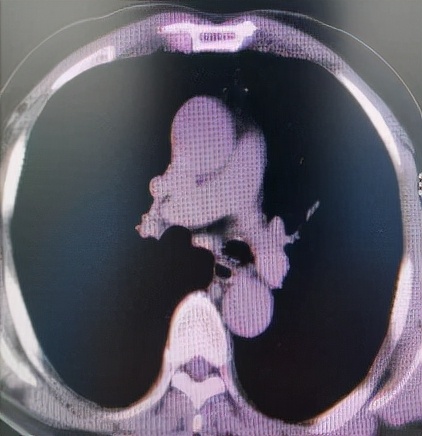

肺 部 C T (削瘤前)

于世寰主任介绍到,患者气管分叉处占位病变面积较大,已累及左、右主支气管,从肺CT影像上判断隆突区病变导致左主支气管狭窄约70-80%左右、右主支气管狭窄约50-60%左右,可操作空间十分有限,支气管镜介入治疗难度较大。隆突区占位病变已累及左右主支气管导致了呼吸困难已不适宜行外科手术治疗,必须通过支气管镜削瘤治疗来解除病人因气道梗阻导致的呼吸困难。支气管镜削瘤治疗与开胸外科手术相比,有痛苦小、创伤小、花费少、可重复性强、并发症少等优点。